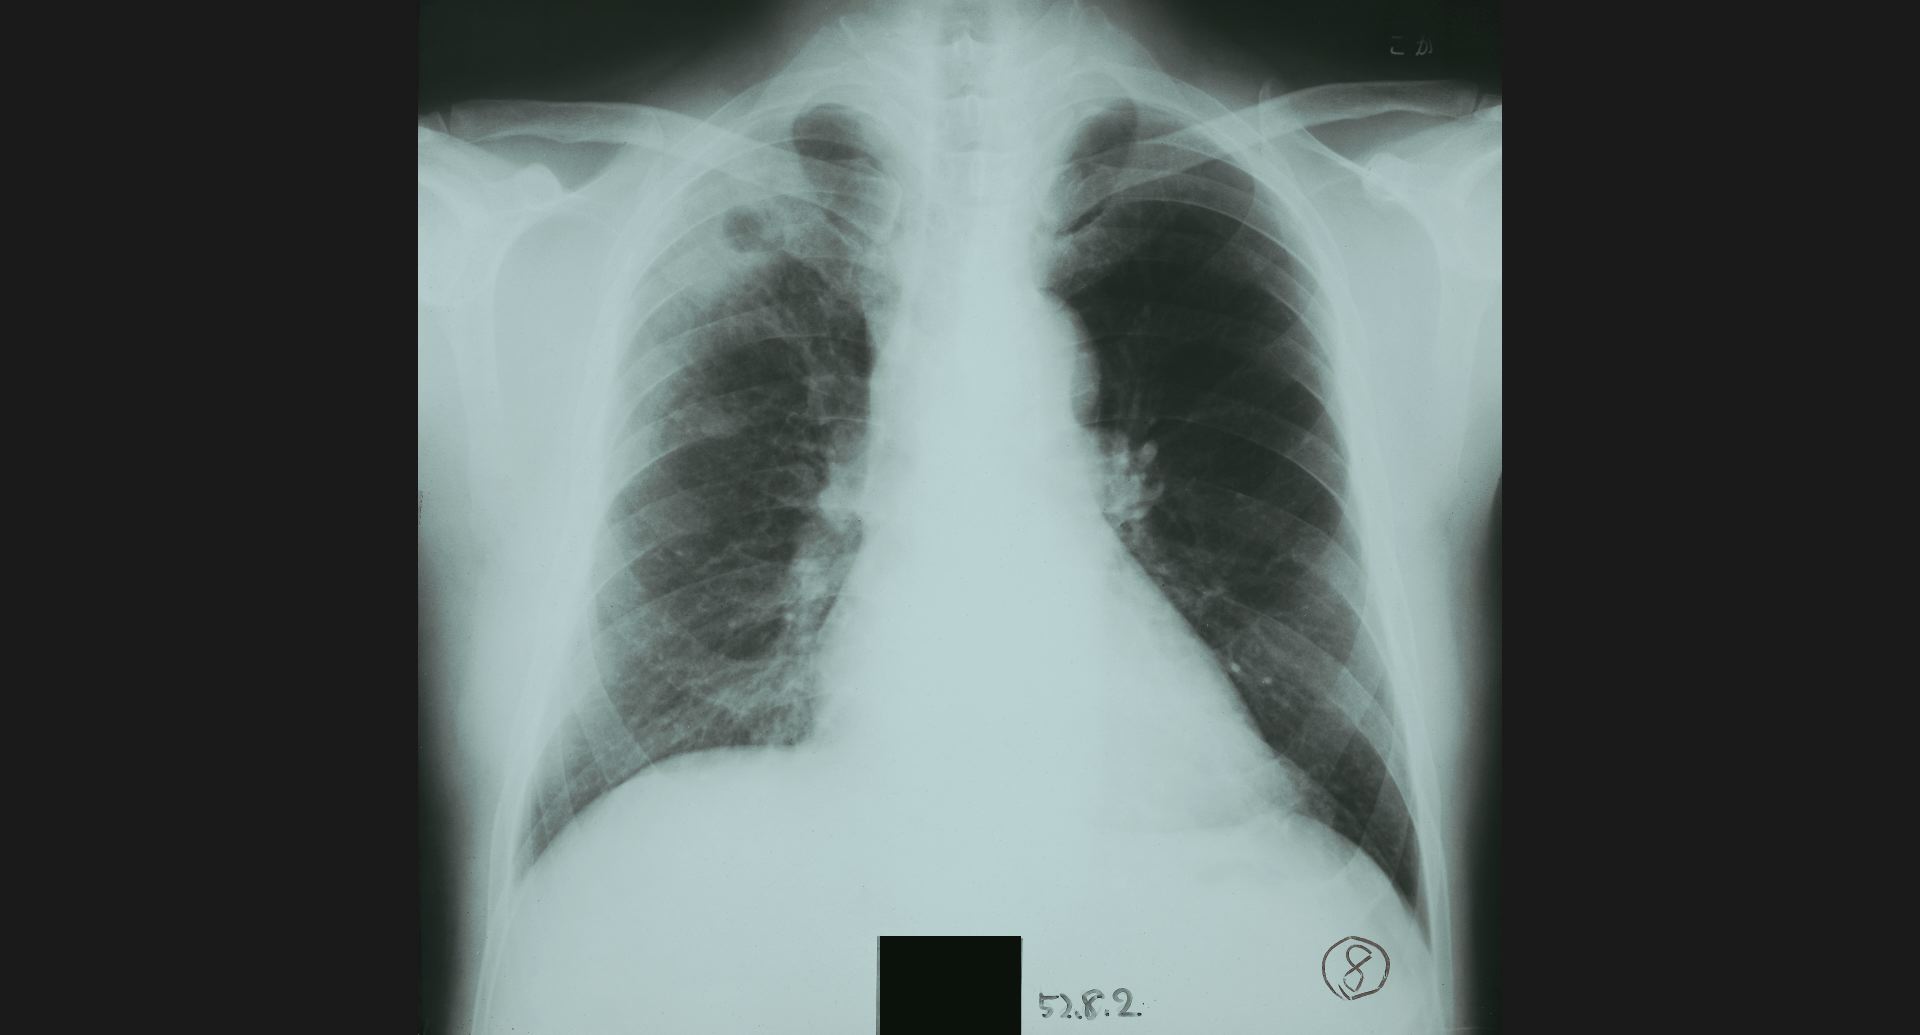

fig.1(117KB)

:Alveolar microlithiasis細かい肺病変、air bronchogram。